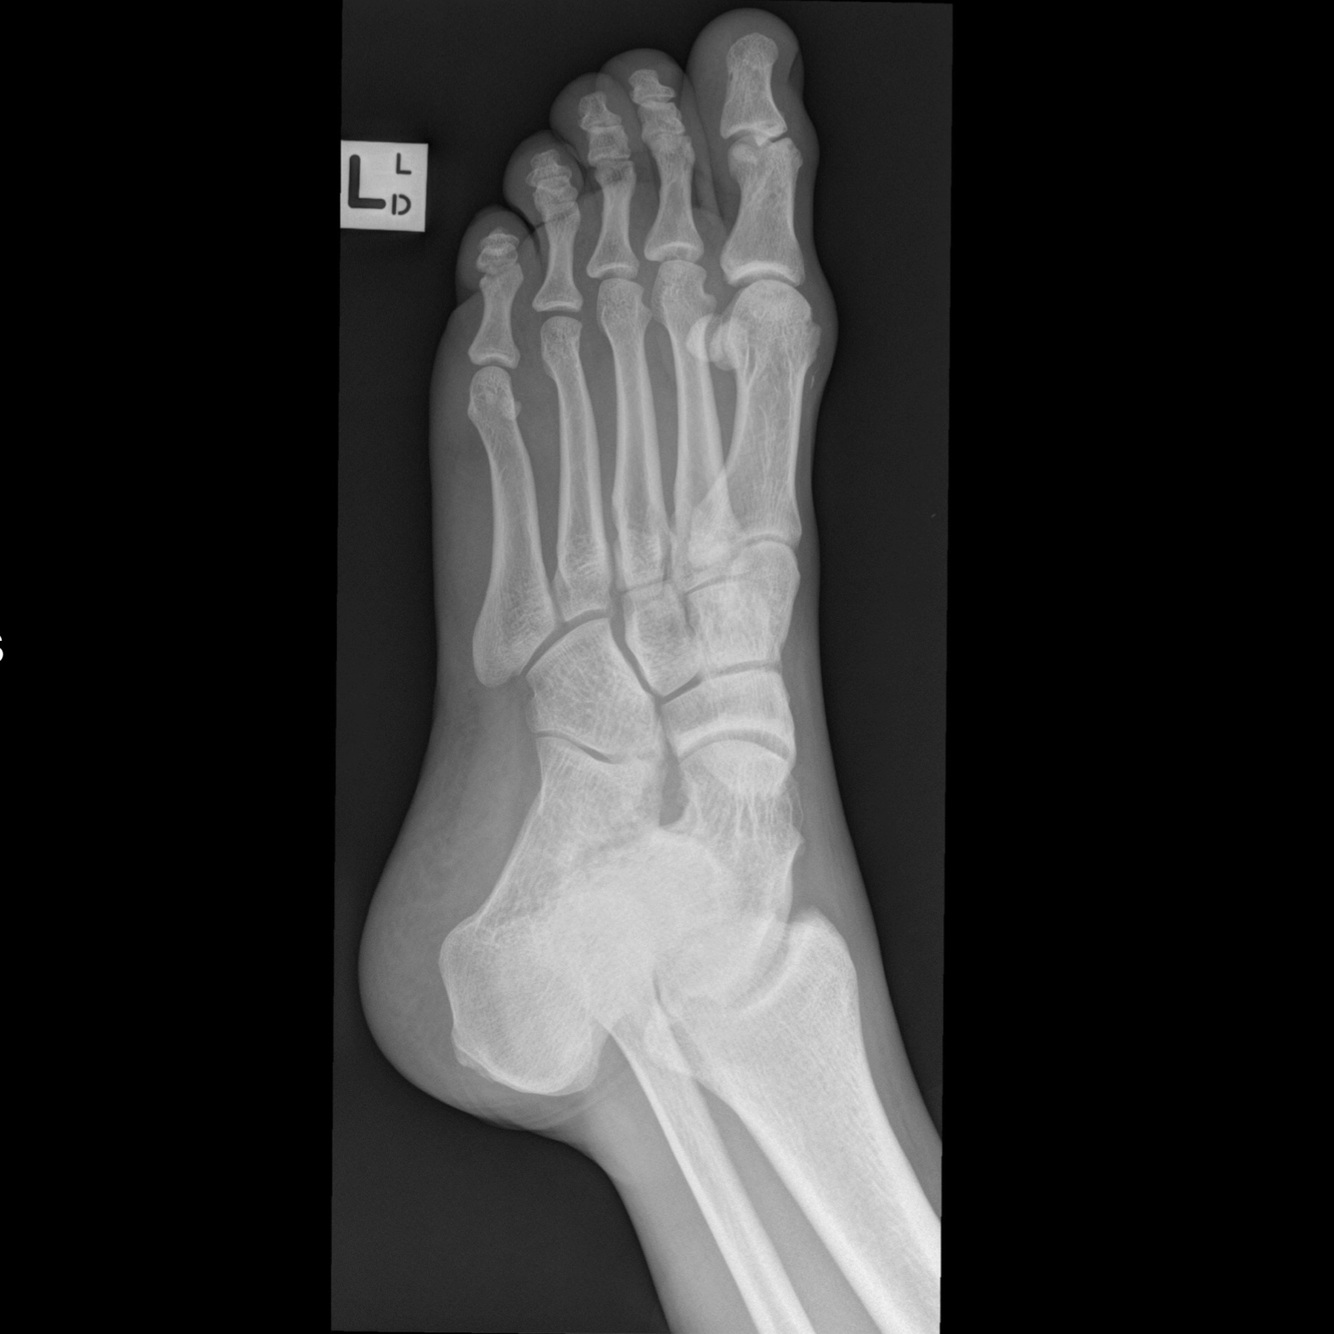

7

Q

Dx?

Et vue?

A

Entorse en éversion avec avulsion (court fibulaire)